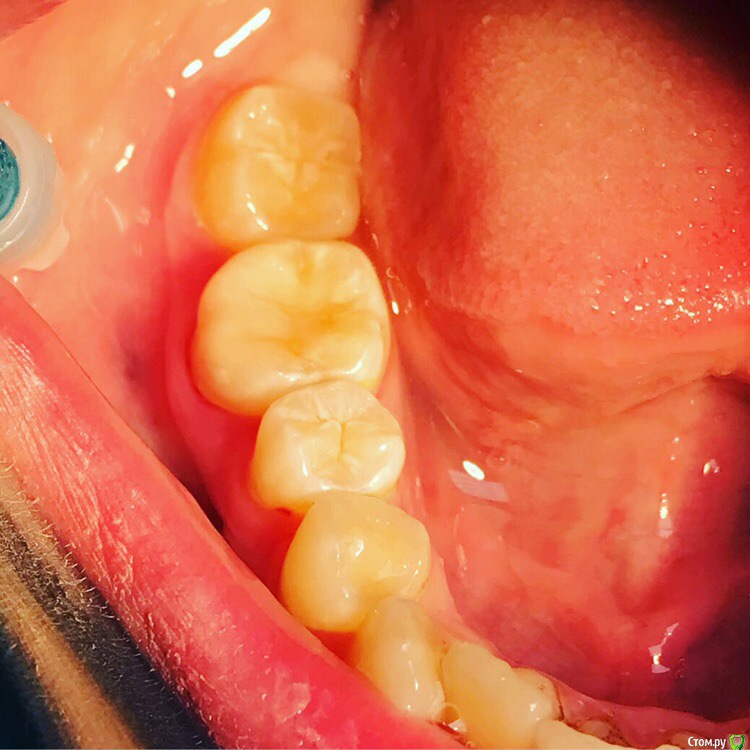

1586Doc Опубликовано 28 марта, 2019 Автор Поделиться Опубликовано 28 марта, 2019 Продолжение 2 Ссылка на комментарий

1586Doc Опубликовано 30 марта, 2019 Автор Поделиться Опубликовано 30 марта, 2019 (изменено) Еще немного работы45 зуб эндо и пломба и 46 зуб эндо и пломба на снимке справа Изменено 30 марта, 2019 пользователем 1586Doc Ссылка на комментарий